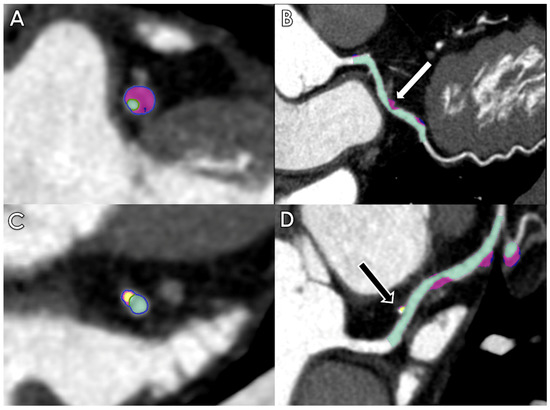

- Choi, A.D.; Marques, H.; Kumar, V.; Griffin, W.F.; Rahban, H.; Karlsberg, R.P.; Zeman, R.K.; Katz, R.J.; Earls, J.P. CT Evaluation by Artificial Intelligence for Atherosclerosis, Stenosis and Vascular Morphology (CLARIFY): A Multi-center, international study. J. Cardiovasc. Comput. Tomogr. 2021, 15, 470–476. [Google Scholar] [CrossRef]

- Hell, M.M.; Dey, D.; Marwan, M.; Achenbach, S.; Schmid, J.; Schuhbaeck, A. Non-invasive prediction of hemodynamically significant coronary artery stenoses by contrast density difference in coronary CT angiography. Eur. J. Radiol. 2015, 84, 1502–1508. [Google Scholar] [CrossRef]

- Griffin, W.F.; Choi, A.D.; Riess, J.S.; Marques, H.; Chang, H.J.; Choi, J.H.; Doh, J.H.; Her, A.Y.; Koo, B.K.; Nam, C.W.; et al. AI Evaluation of Stenosis on Coronary CT Angiography, Comparison With Quantitative Coronary Angiography and Fractional Flow Reserve: A CREDENCE Trial Substudy. JACC Cardiovasc. Imaging 2022, 16, 193–205. [Google Scholar] [CrossRef] [PubMed]

- Yi, Y.; Xu, C.; Guo, N.; Sun, J.; Lu, X.; Yu, S.; Wang, Y.; Vembar, M.; Jin, Z.; Wang, Y. Performance of an Artificial Intelligence-based Application for the Detection of Plaque-based Stenosis on Monoenergetic Coronary CT Angiography: Validation by Invasive Coronary Angiography. Acad. Radiol. 2022, 29 (Suppl. 4), S49–S58. [Google Scholar] [CrossRef] [PubMed]